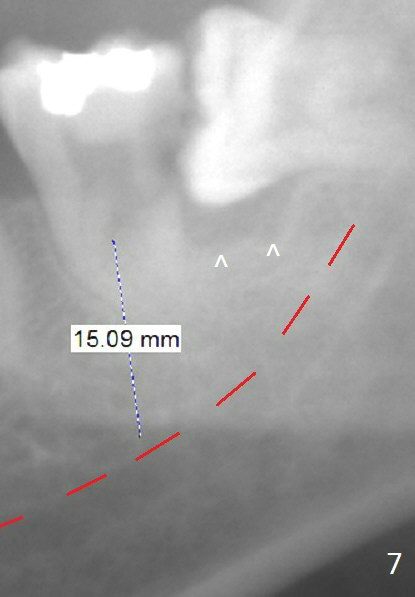

In fact, RCT is tried. Fourteen months later, the tooth remains symptomatic with mobility (Fig.6). Due to the distal defect caused by the 3rd molar (Fig.6,7 arrowheads), the implant should be placed as mesial and deep as possible.